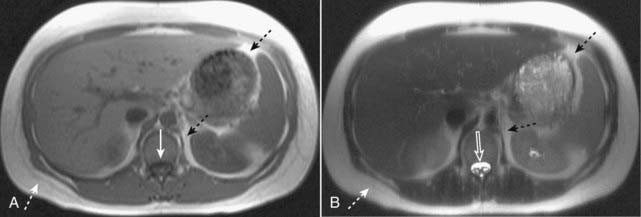

If the fluid is dark, then you are probably looking at a T1-weighted sequence (Fig. 20-1A).

If this fluid is bright, then chances are you are looking at a T2-weighted image (Fig. 20-1B).

Figure 20-1 Normal T1-weighted and T2-weighted axial images of the abdomen.

Because cerebrospinal fluid is similar to water in density, it appears dark on the T1-weighted image (A) (solid white arrow), and bright on the T2-weighted image (B) (open white arrow). Subcutaneous fat (dotted white arrows) and intraabdominal fat (dotted black arrows) are bright on both T1-weighted and T2-weighted images.